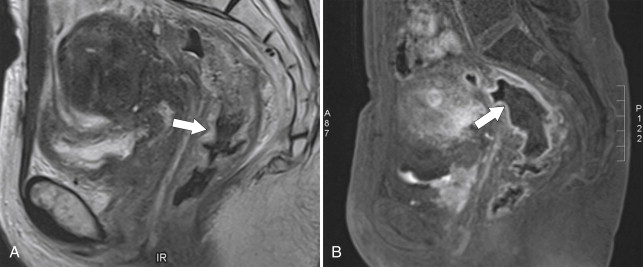

The findings are most often visualized by CT, particularly because patients are often serially imaged to evaluate for any local cancer recurrence or metastatic disease, although MRI often detects more subtle changes ( Fig. 5-40 ). Associated inflammatory changes are often observed in the surrounding mesentery (fat-stranding). This is commonly seen in the presacral region after radiation for rectal cancer preceding attempted surgical removal of the tumor. Radiation changes can sometimes be difficult to differentiate from local recurrence, but awareness that the patient has undergone radiation should alert the radiologist that the changes are benign rather than malignant recurrence. Increasingly, PET imaging is used to differentiate postradiation changes from recurrent disease ( Fig. 5-41 ).

Figure 5-40, Sagittal T2-weighted ( A ) and contrast-enhanced MRI ( B ) in a 47-year-old woman with rectal wall thickening ( arrow ) and mucosal hyper-enhancement due to radiation colitis ( arrows ).